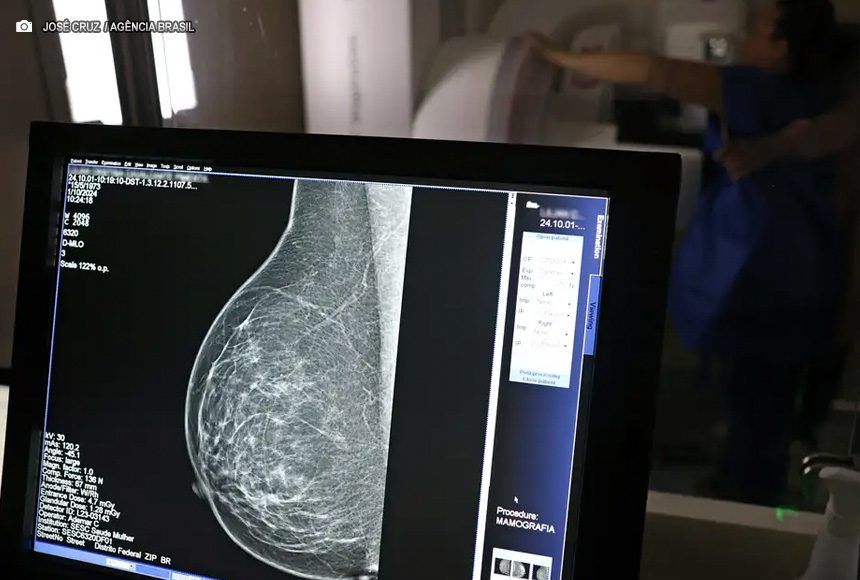

No mesmo local, a dona de casa Lilian Cristina Cavalcanti, fez pela primeira vez uma mamografia, a radiografia específica das duas mamas que possibilita a identificação precoce de alterações nos seios. Com 51 anos e mãe de três filhos, ela admite que, até hoje, deixou a questão de lado por falta de tempo e por achar que seria difícil conseguir a vaga em uma unidade pública de saúde. “Nunca tentei. Não tenho paciência para ficar na fila esperando e, como nunca senti nada [no autoexame da mama], deixei passar”, confessou.

Mas, chegou a hora dela realizar a mamografia bilateral. Lilian Cristina se posicionou em pé, em frente ao aparelho e, imóvel, teve as mamas comprimidas em diferentes ângulos para captura das imagens detalhadas. No fim, ela saiu da carreta do Sesc com impressões positivas sobre o exame. “Achei que doía mais, mas foi bem tranquilo. Agora, espero ansiosa pelo resultado do exame.”

André Abreu, do Sesc-DF, explica que as imagens em alta resolução captadas pelos mamógrafos são enviadas automaticamente aos profissionais do Hospital de Barretos (SP) para análise e emissão do laudo médico, em até 30 dias. “Se o laudador já identificar visualmente um câncer, ele avisará a equipe de Brasília que poderá ter que repetir o exame e esta deverá encaminhar a mulher examinada como paciente ao Hospital de Base de Brasília”. Nos demais casos, quando for constatada a normalidade das mamas, a mulher receberá o laudo em um envelope nominal no prazo citado, no mesmo local – a rodoviária do Plano Piloto.

A mamografia de rastreamento de doenças deve ser feita a cada dois anos e é indicada para mulheres a partir de 50 anos. Porém, o risco é mais elevado de ocorrência em pessoas com histórico familiar de câncer de mama.

O técnico em radiologia Ademar Cardoso revelou que, nos dez anos de atuação na área, muitas vezes percebeu a presença de nódulos nas mamas de pacientes ainda no momento de realização da mamografia e comenta a relevância da prevenção. “Muitas vezes vejo pessoas sem informação e, por isso, o exame de graça é tão importante, porque é feito o encaminhamento necessário e a paciente pode dar início a tratamento, quando for o caso.”